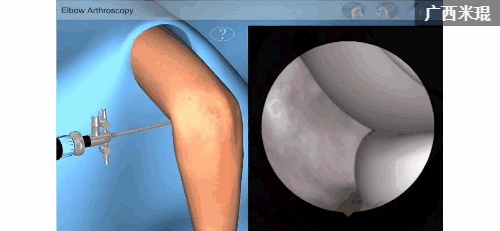

关节镜技术的发展是技术的进步、病人的需求以及医生对微创理念执着追求的结果,相对于膝、肩等关节而言,肘关节的解剖结构复杂,肘关节镜技术的难度极大,以致于在骨科文献中曾提及“肘关节不适于关节镜检查”!但随着手术技术发展、设备的改善、临床经验积累、手术体位和手术入路的改进,肘关节镜手术的危险程度已经大大降低,手术指征不断得到拓展,技术日渐成熟,近几年来肘关节镜技术更是得到迅速发展,造福了广大肘关节伤病患者。

肘关节镜的手术入路有很多,如中外侧入路(软组织点)、后正中入路、后外侧入路、近端前外侧入路、前外侧入路、外侧垂直入路、近端前内侧入路、前内侧入路等,一般选择2-3个入路就能完成手术。入路不但要清晰显示并方便处理肘关节的病变,更主要的是要确保安全!